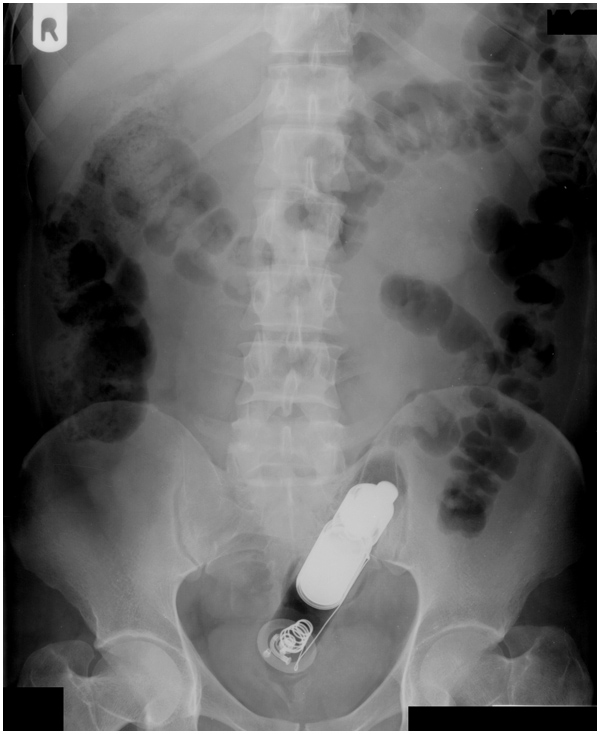

Und wenn ich mir das so ansehe und das mit der Notaufnahme in Verbindung bringe, braucht es jetzt nicht viel Fantasie, um sich vorzustellen, was da sonst noch so passieren kann..

Ich schlage einen Dremel vor. Funktioniert ganz gut. Der Beweis:

Zur Klarstellung die Zweifel oder einfach nur unwissend sind! Nun mit einer Märchenstunde oder einem Wunschkonzert hat dies nichts zu tun! Falls jemand wissen möchte wo wie und was anbei ein Bild mit den Maaßen kann man käuflich bei den üblichen Chinesen bestellen und bevor nun wieder ohhh China kommt meine Gesundheit nicht die von jemandem der zweifelt ! Und ja dieser geht ganz rein ist eigentlich schon zu kurz !